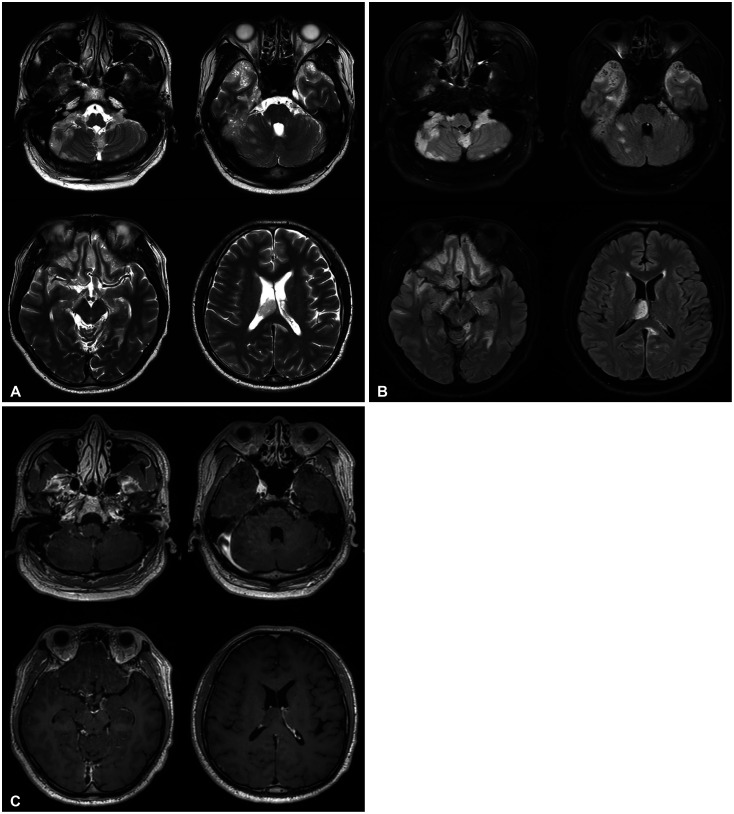

室管膜瘤是一种罕见的成人肿瘤,起源于中枢神经系统的室管膜细胞,主要发生在脑室或脊髓中央管。在这篇文章中,我们报告一个39岁的男性患者,在头部外伤后偶然发现了广泛的室管膜瘤。MRI表现为弥漫性脑脊膜浸润性病变,伴双侧多脑沟、基底池、桥小脑角、小脑叶。它还显示沿整个脊髓的多结节增强T1低T2高信号强度病变。右侧颞叶病变肿瘤活检后,病理诊断为典型室管膜瘤(WHO分级2级)。患者接受放疗和化疗,术后2年病情稳定。本报告提示,在考虑颅内和椎管间隙广泛病变的鉴别诊断时,也应考虑室管膜瘤。

Ependymoma is a rare adult tumor that originates from ependymal cells of the central nervous system, primarily occurring in the cerebral ventricles or the central canal of the spinal cord. In this paper, we report a case of extensive leptomeningeal seeding of ependymoma of a 39-year-old male patient, in whom the tumor was found incidentally after head trauma. The MRI exhibited diffuse leptomeningeal infiltrative lesions along with bilateral multiple cerebral sulci, basal cisterns, cerebellopontine angle, cerebellar folia. It also showed multinodular enhancing T1 low T2 high signal intensity lesions along the whole spinal cord. After the tumor biopsy at right temporal lesion, pathologic diagnosis was classic ependymoma (WHO grade 2). The patient has undergone radiation therapy and chemotherapy, and is currently maintaining a stable condition two years after surgery. This report suggests that when considering the differential diagnosis of extensive lesions both in the intracranial and intraspinal space, ependymoma should also be considered.